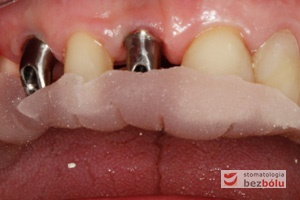

Filary protetyczne przygotowane do pobrania wycisku - transfery wyciskowe typu "bałwanek" przykręcone do implantów - zęby po redukcji dziąsła

Filary protetyczne przygotowane do pobrania wycisku – transfery wyciskowe typu „bałwanek” przykręcone do implantów – zęby po redukcji dziąsła

Transfery wyciskowe - widok z przodu - przenośniki typu "bałwanek" dedykowane pojedynczym implantom

Transfery wyciskowe – widok z przodu – przenośniki typu „bałwanek” dedykowane pojedynczym implantom